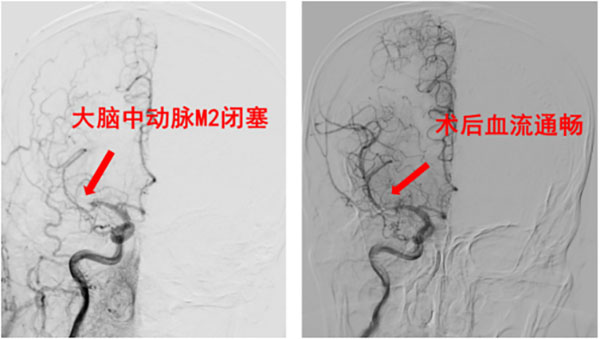

病例4——醒后卒中,延误治疗的教训:(54岁男性)患者夜间醒后自觉言语迟钝,自认为未休息好,未予重视。2小时后晨起时发现左侧肢体活动明显障碍、行走不稳,才紧急就医。此时距首次发现症状已过去10小时。检查提示右侧大脑中动脉M2闭塞,虽经急诊取栓成功再通,但延误的时间可能已导致部分脑组织不可逆损伤。此病例再次敲响警钟:夜间或晨起出现的任何异常,都可能是卒中信号,切莫等待!